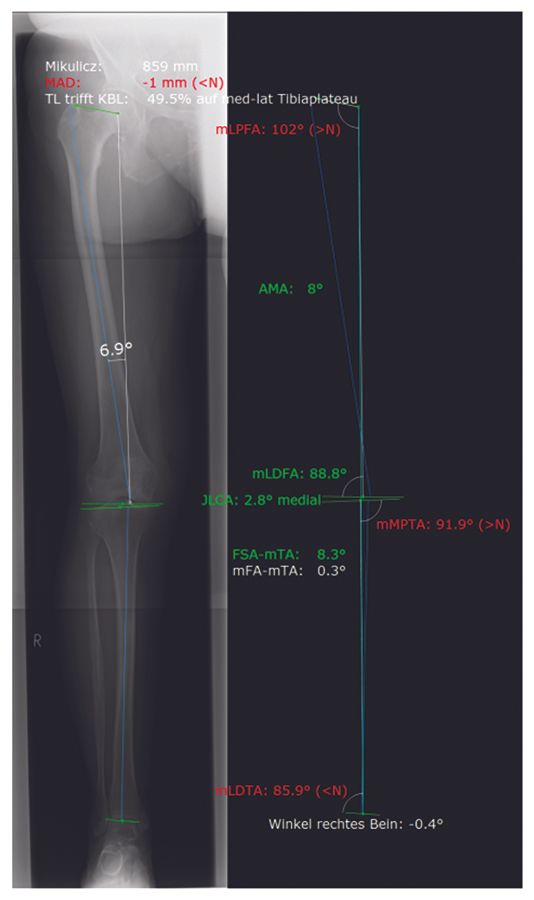

All patients undergo standard anteroposterior and lateral view radiography and a full long leg (hip-knee-ankle angle [HKA]) standing radiograph. The mechanical medial proximal tibia angle (mMPTA) and the mechanical lateral distal femur angle (mLDFA) are evaluated in order to differentiate between osteoarthritis-based varus and bony varus deformity.

MediCAD (mediCAD Hectec GmbH) is used for preoperative planning (Figure 2). Surgical planning begins with a neutral hip-knee-ankle angle in the coronal plane. In the sagittal plane, 4° femoral component flexion in relation to the femoral sagittal mechanical axis and 3° tibial slope are targeted. Femoral rotation parallel to the anatomical (true) TEA is set intraoperatively by identifying the medial and lateral epicondyles. A medial parapatellar approach is used for all surgeries.

Approximately 600 patients were operated in our clinic with the balanced gap technique presented in this paper. In this patient cohort, the HKA changed from -6.7° ± 3.6° (range, -0.5 to -19°) preoperatively to -2.9° ± 2.1° (range, -0.5 to -5.5°) postoperatively. Hence, a residual varus was seen in all patients (Figures 15 - 16).